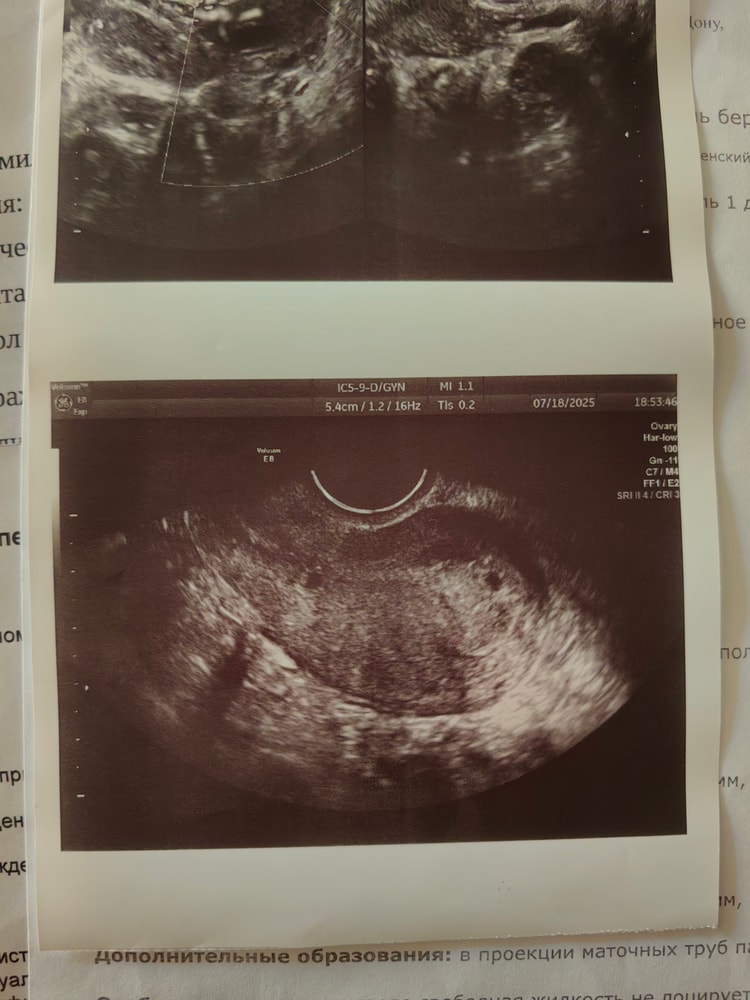

На узи сходила в 6 недель и 2 дня по календарю, нашли пя 3,9мм и желточный мешочек 1,2мм. Узистка сказала что должно быть 6 недель и 2 дня, но по узи всего 3, возможно из-за поздней овуляции (на узи просто видно было как чёрное пятнышко и всё). Тогда кровь на хгч не сдавала.

Анастасия, у вас там не 2 ПЯ случаем?

Bandy, я тоже про это думала в день узи, чуть мозг не сломала. На след день у гинеколога спросила, она сначала в ступор встала, потом сказала что это не пя, то что слева не может там находиться, ну и всё. А так изначально была надежда что их было 2 и 1 не прижился, но при двойне наоборот хгч больше должен быть, поэтому вообще ничего не сростается

Анастасия, ну эти образования очень похожи на ПЯ малого срока и они оба в матке. Она все равно должна была описать, что это такое, а получается - проигнорировала.

Bandy, так вроде бы как и похоже по размеру, на 5 недель вроде не тянет эта чёрная точечка. Вообщем как-то всё сложно, несколько дней голову ломаю, побыстрее бы уже получить результат второго хгч

Анастасия, как раз на 5 недель и тянет. Где указан срок 3 недели - это то же самое что 5 в акушерстве.

У меня при хгч около 2000 тыс увидели пя 3 мм и то под вопросом. Тут при таком маленьком хгч увидеть, еще и жм- очень странно. Либо увидели что то другое...

Хгч 206 ? Если да , то он падает у вас. ПЯ видно при хгч от 1000-1500, и если оно у вас уже было 3,9 мм , значит хгч был больше 1000

С таким хгч пя не видно,значит хгч был больше и уже падает,раз пя нашли,пя 3,9 это хгч около тысячи+ пересдайте хгч

При хгч 2500 было пя 4 мм,при 200 такого пя быть не может,если лаборатория не ошиблась,то хгч падает,был выше,хгч 200 был на 14 дпо это 2 недели от овуляции,никакого пя ещё видно не было,а у вас пя на 3 недели от овуляции,а хгч на 2, скорее всего упал